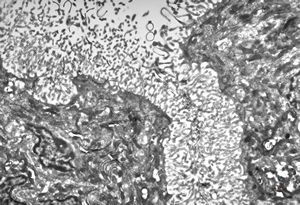

F,23y. | - n.suralis- hypertrophic demyelinizing neuropathy (onion bulbs)